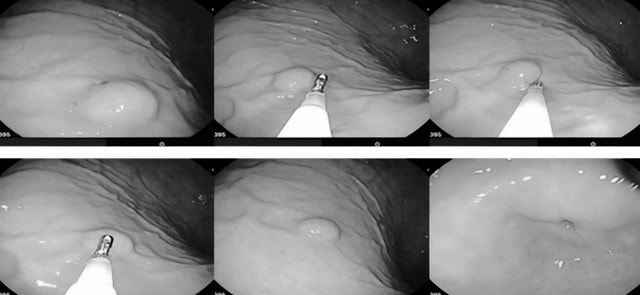

Các bác sĩ tiến hành rạch một đường niêm mạc ở vùng cách xa tổn thương (thông thường cách khối u khoảng 1–5 cm), sau đó đưa ống nội soi vào lớp dưới niêm mạc và di chuyển dần về vị trí khối u, tạo thành "đường hầm" để tiếp cận. Sử dụng kỹ thuật phẫu tích cắt dưới niêm mạc (ESD) để cắt bỏ toàn bộ khối u một cách chính xác. Sau khi đã cắt bỏ hoàn toàn khối u, bác sĩ tiến hành đóng đường rạch niêm mạc bằng clip.